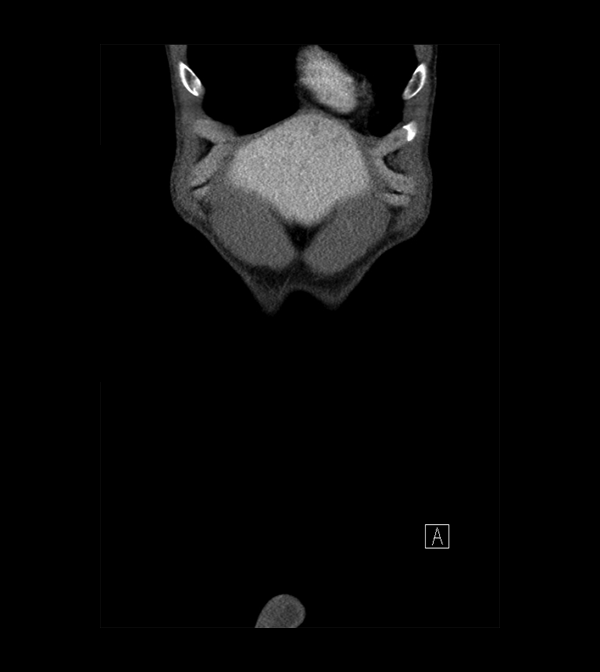

Pelvis

Covers pelvic MRI anatomy.